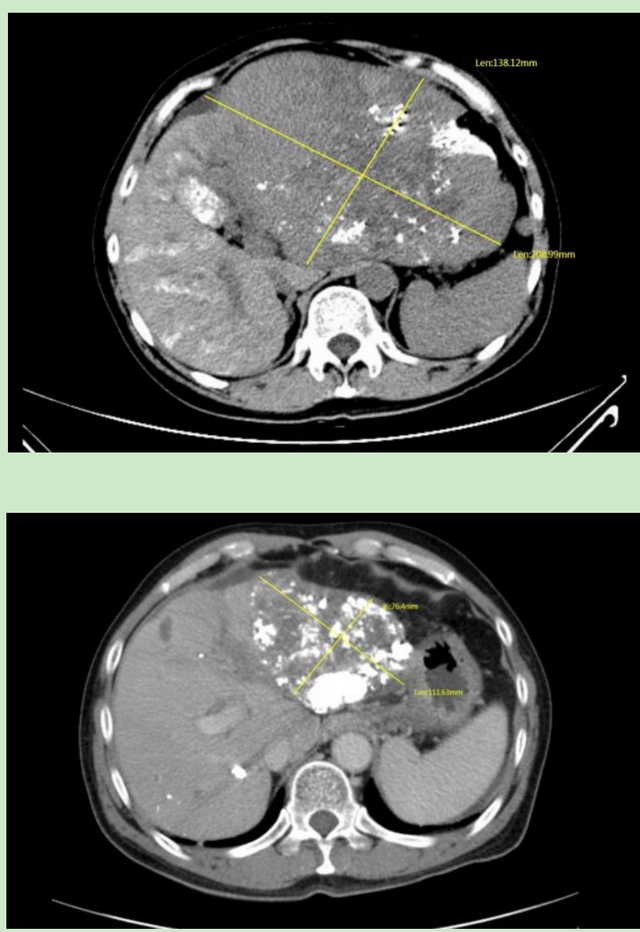

经过多次调整治疗方案,患者肿瘤缩小至原肿瘤的一半

肿瘤相关指标的不断好转,让老吴越来越有信心。经过1年治疗,2021年4月复查结果显示,老吴甲胎蛋白从最高16950μg/L降至8.1μg/L,肝左叶肿物明显缩小,双肺多发小结节以及上纵膈、腔静脉后增大的淋巴结也都明显缩小,这意味着老吴的手术机会来了。